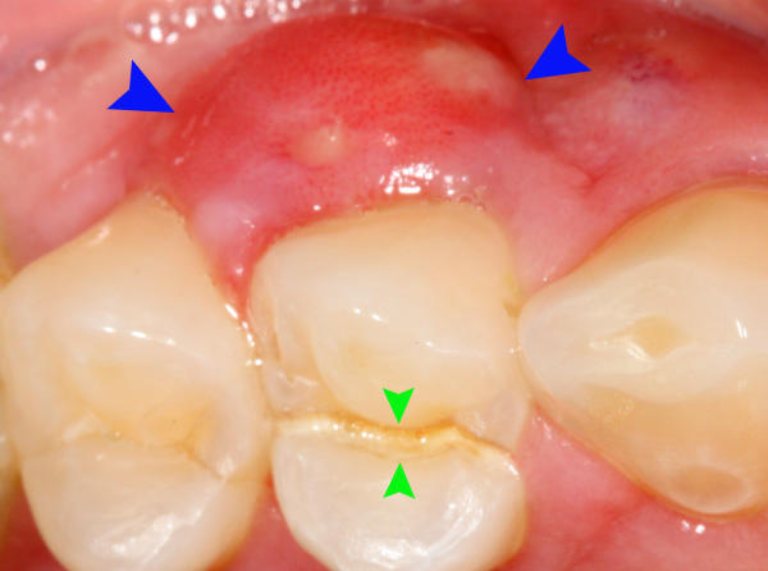

Xương hàm ở vị trí mất răng chưa bị tiêu hõm, không viêm lợi hay viêm quanh răng

Một yếu tố quan trọng khác khi quyết định làm cầu răng sứ là tình trạng của xương hàm. Xương hàm tại vị trí mất răng cần phải ổn định và chưa bị tiêu hõm. Tiêu hõm xương xảy ra thường xuyên khi mất răng mà không có sự can thiệp kịp thời, dẫn đến việc cấu trúc xương không còn vững chắc. Điều này có thể làm giảm khả năng trụ của cầu răng.

Ngoài ra, tình trạng viêm lợi cũng cần được xem xét. Nếu khu vực quanh vùng mất răng có dấu hiệu viêm nhiễm, việc thực hiện cầu răng sứ có thể gây ra các biến chứng nghiêm trọng và không đạt được hiệu quả như mong muốn.